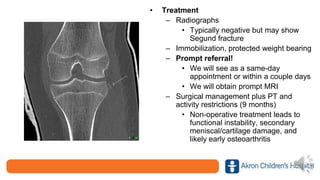

• Treatment

– Radiographs

• Typically negative but may show

Segund fracture

– Immobilization, protected weight bearing

– Prompt referral!

• We will see as a same-day

appointment or within a couple days

• We will obtain prompt MRI

– Surgical management plus PT and

activity restrictions (9 months)

• Non-operative treatment leads to

functional instability, secondary

meniscal/cartilage damage, and

likely early osteoarthritis

• Treatment – Radiographs •Typically negative but may show Segund fracture – Immobilization, protected weight bearing – Prompt referral! • We will see as a same-day appointment or within a couple days • We will obtain prompt MRI – Surgical management plus PT and activity restrictions (9 months) • Non-operative treatment leads to functional instability, secondary meniscal/cartilage damage, and likely early osteoarthritis